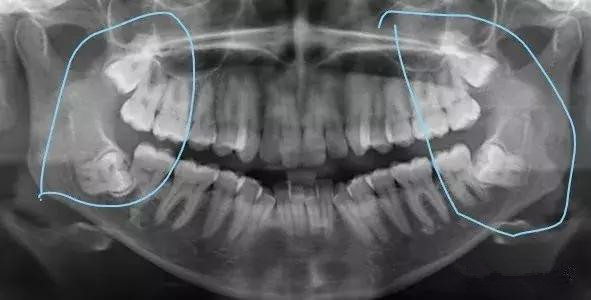

总结来说,下颌智齿有七种方法让你跪下叫爸爸(点开原图放大,对号入座):

七种最常见的是近中阻生和水平阻生

最极品的就是倒置阻生了